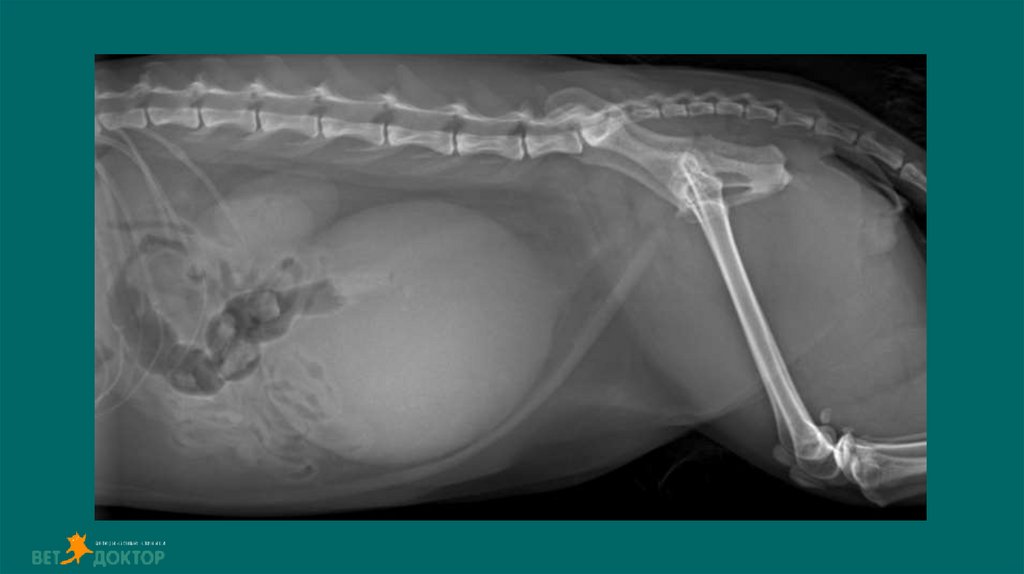

Тотальный гидронефроз

Терапия ОПП

Гемотрансфузия рекомендована, улучшает перфузию почек и доставку кислорода Противопоказания: острый